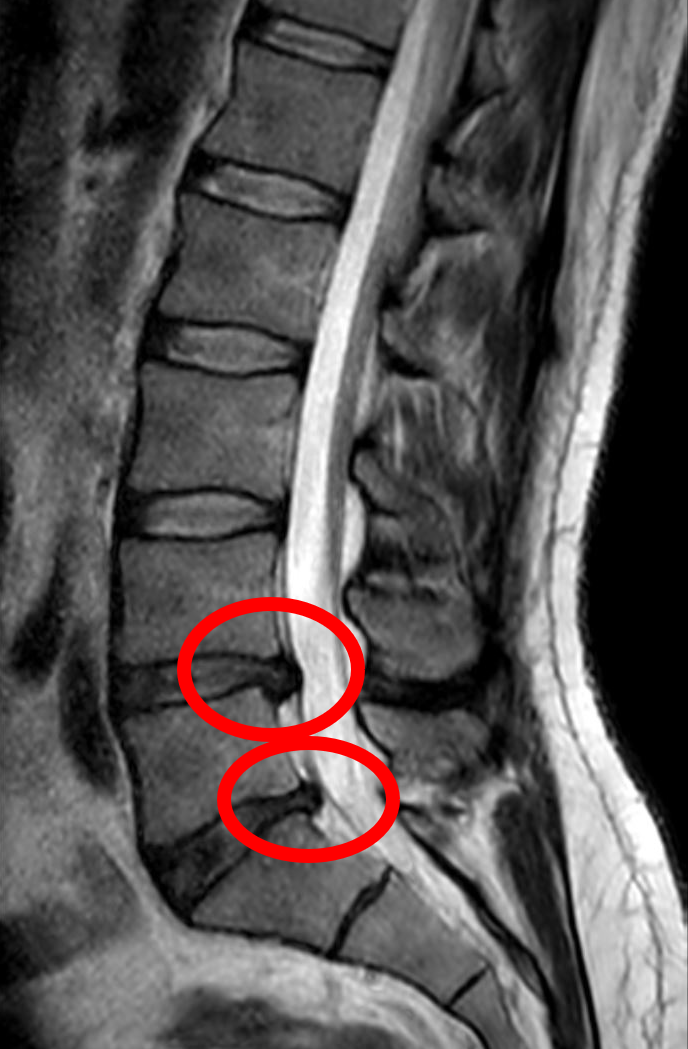

L4-L5 posterolateral disc herniation compressing the L5 nerve root with disc desiccation, annular tear, and...

Lumbar spinal stenosis with ligamentum flavum hypertrophy, facet joint arthropathy, disc bulge, and narrowed central canal